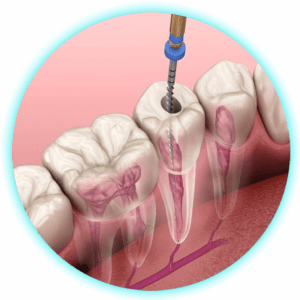

Endodoncia Multiradicular

$200,00 -

Endodoncia Uniradicular

$170,00 -

Pulpectomía (Endodoncia en niños)

$100,00 -